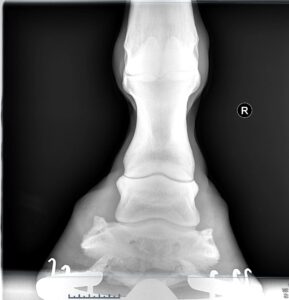

Radiography (X-rays)

Our portable digital x-ray system allows us to take high-quality images on your premises.

X-rays allow us to assess bones and joints in detail. They are invaluable for diagnosing lameness, fractures, arthritic changes, foot balance issues, and dental or sinus problems.

Your vet will position a small plate behind the area being imaged and stand at a safe distance while the x-ray is taken. Most horses tolerate the procedure well, and results are available immediately.